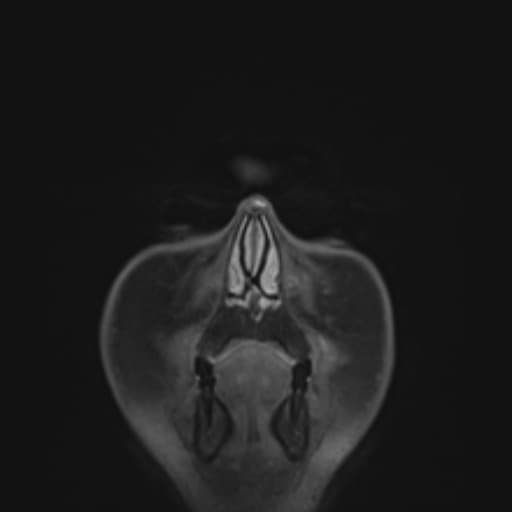

MRI

MRI nhạy hơn CT. Mặc dù các tổn thương viền ngấm thuốc có thể không đặc hiệu trên hình ảnh, nhưng các dãy hình khuếch tán (ít phổ biến hơn là phổ cộng hưởng từ – MR spectroscopy) cho thấy hạn chế khuếch tán ở trung tâm là yếu tố then chốt gợi ý chẩn đoán áp xe não.

T2/FLAIR

trung tâm tăng tín hiệu (giảm tín hiệu so với dịch não tủy, không giảm tín hiệu trên FLAIR)

vùng ngoại vi tăng tín hiệu (phù vận mạch)

vỏ bao áp xe có thể thấy như một viền mỏng có tín hiệu trung gian đến hơi giảm 1